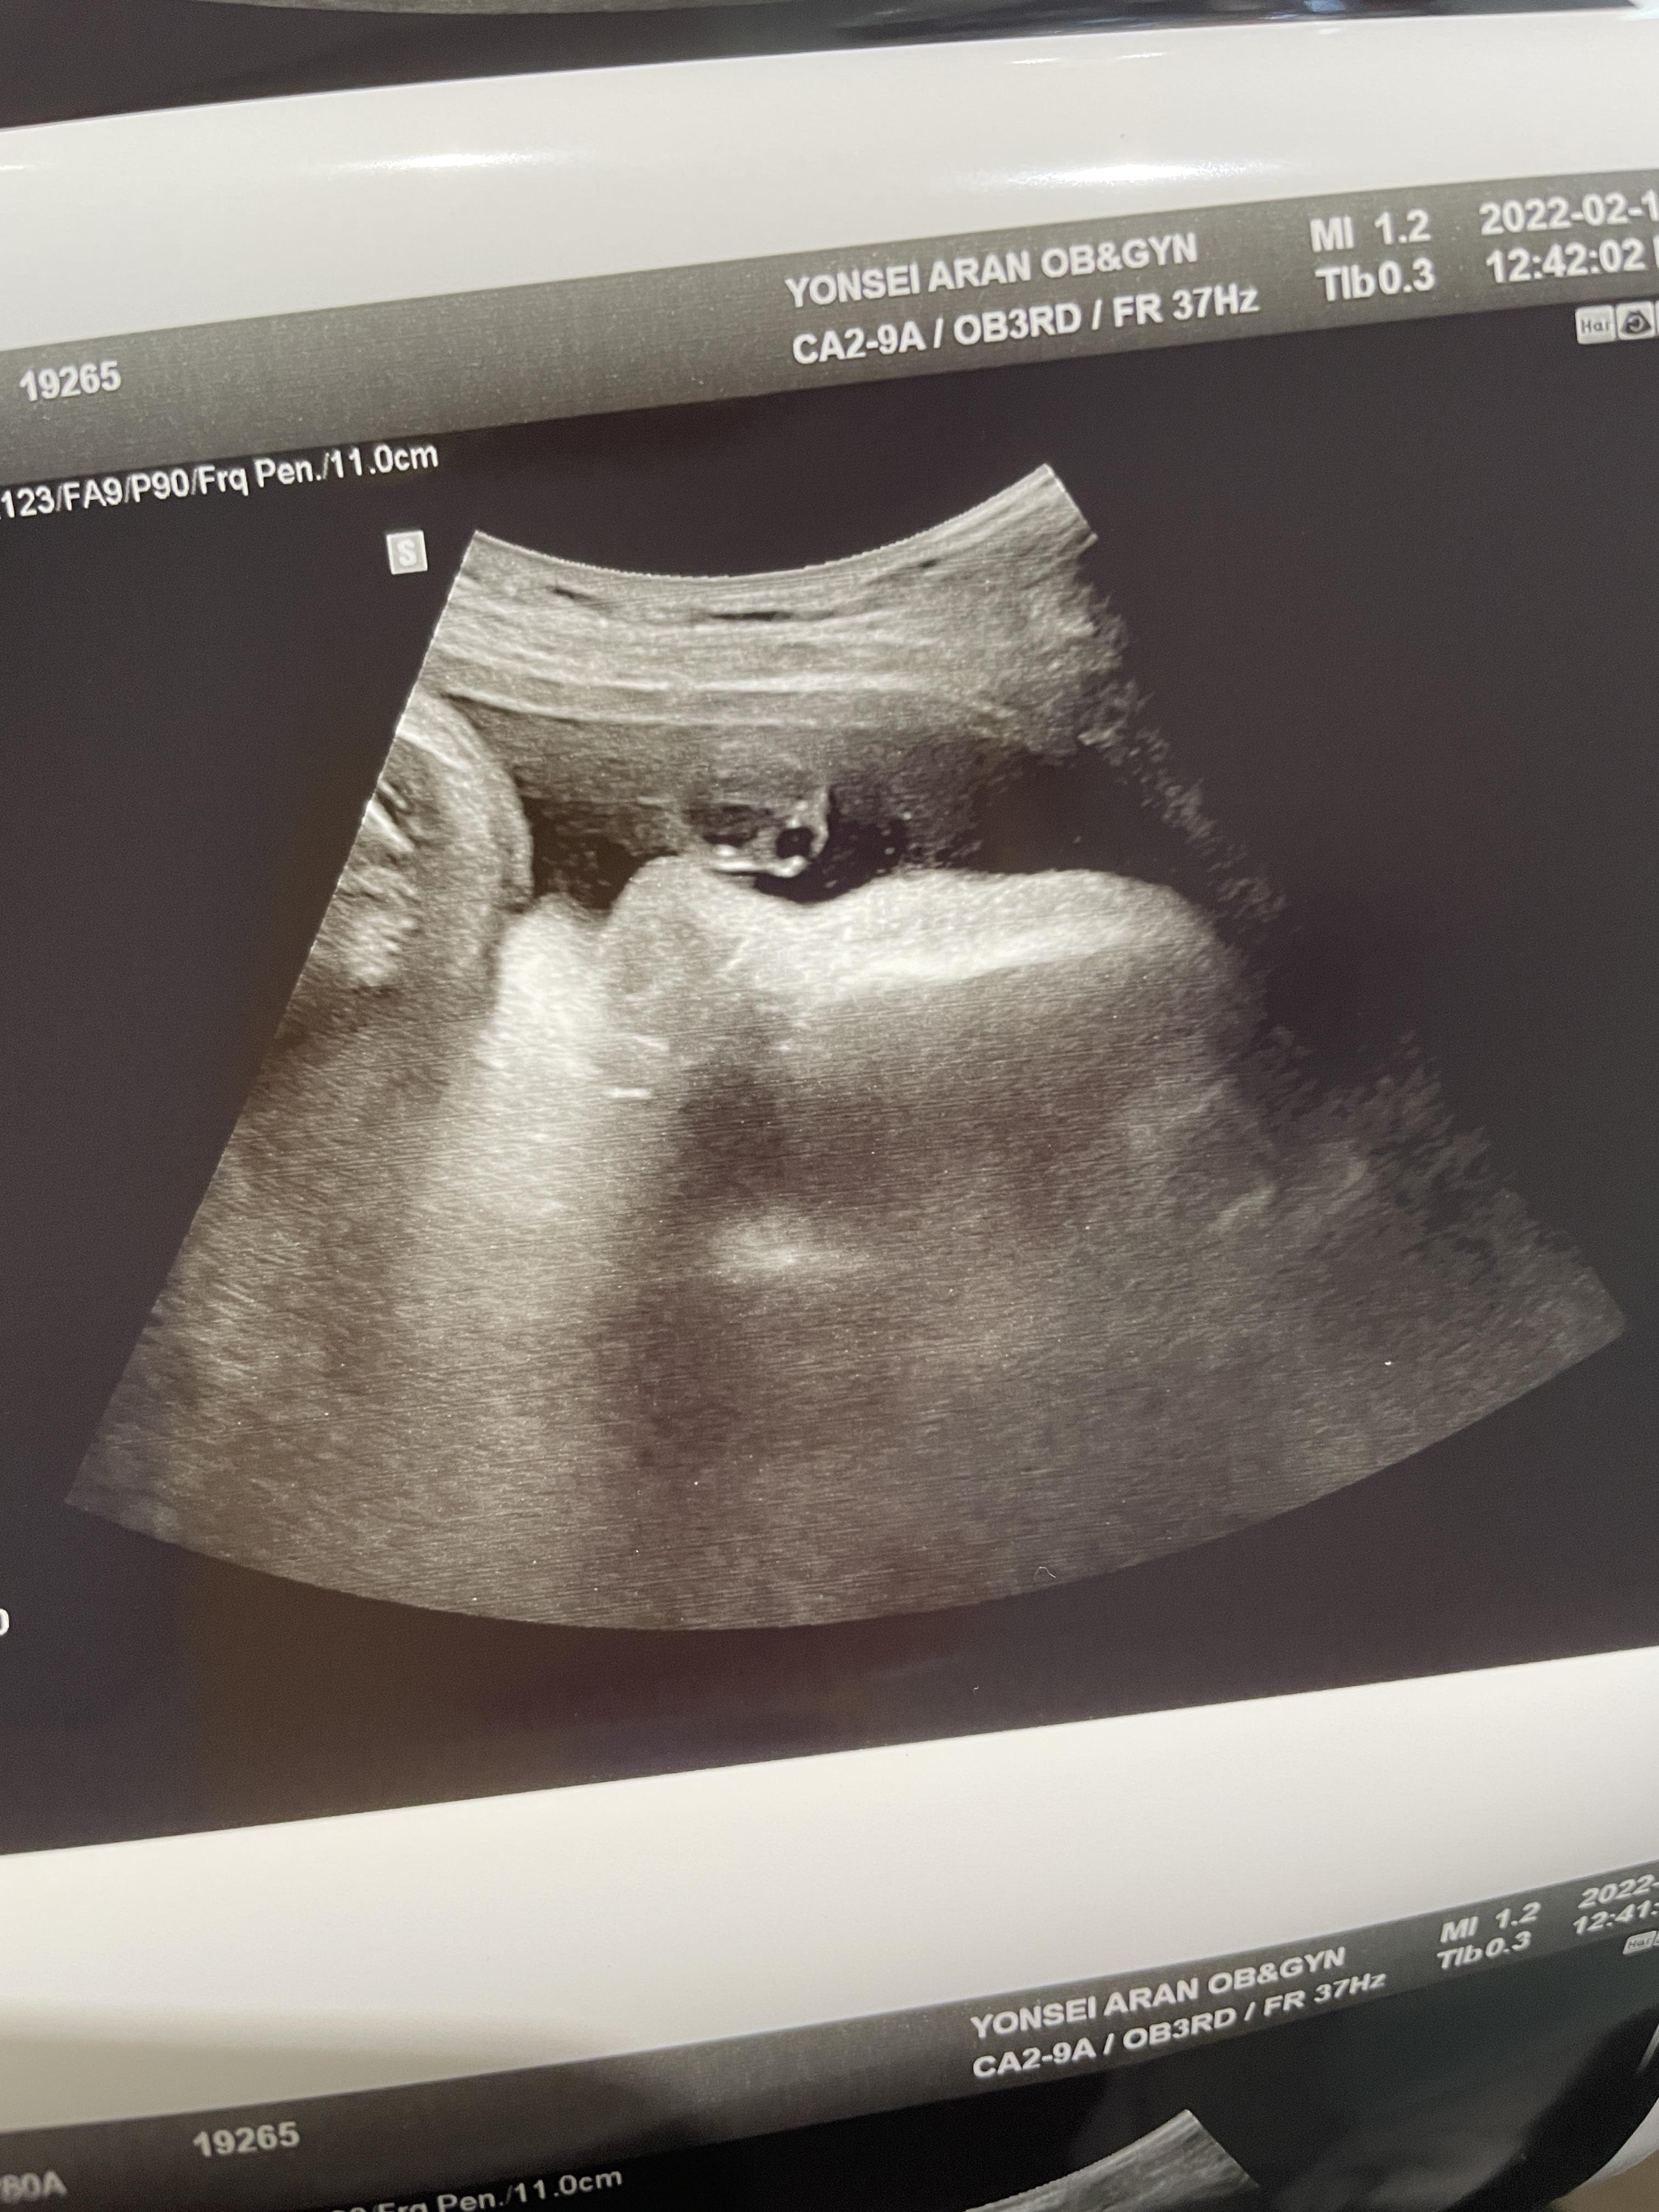

애기가 얼굴이 너무 잘보인다며 웃으셨다.

하나도 안내려왔다고...ㅠ

그와중에 머리는 역시 커졌고,